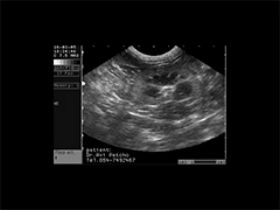

אולטראסאונד אצל כלבה עם דלקת כרונית של כיס המרה (מימין) ווריד נבוב מורחב מאד. הכלבה הייתה חולה בסכרת על רקע הורמונאלי עקב גידול ממאיר של הלבלב